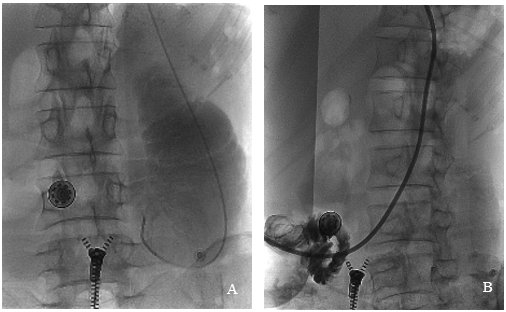

不过,她的梗阻不是完全「死」的,而是留下了一道几乎无法察觉的「缝隙」。要打通它,唯一的希望是微创介入——用比头发丝还细的导丝,在这片「迷宫」中找到正确的路径。

合肥京东方医院肿瘤放疗科联合影像科韦树华主任、肿瘤科介入治疗组,像刑侦专家一样,对着患者的片子反复研判,终于在错综复杂的影像中,锁定了那条理论上可行的「生命缝隙」。真正的挑战,在手术台上。介入治疗组专家孙东旭,操控着两根导丝开始 「探险」:

术后,患者成功实现了经鼻饲管输入肠内营养液且无呕吐,这不仅让她逐步摆脱住院完全依赖输液的日子,更意味着身体有了承受后续抗癌治疗的「本钱」,是康复路上的关键一步。